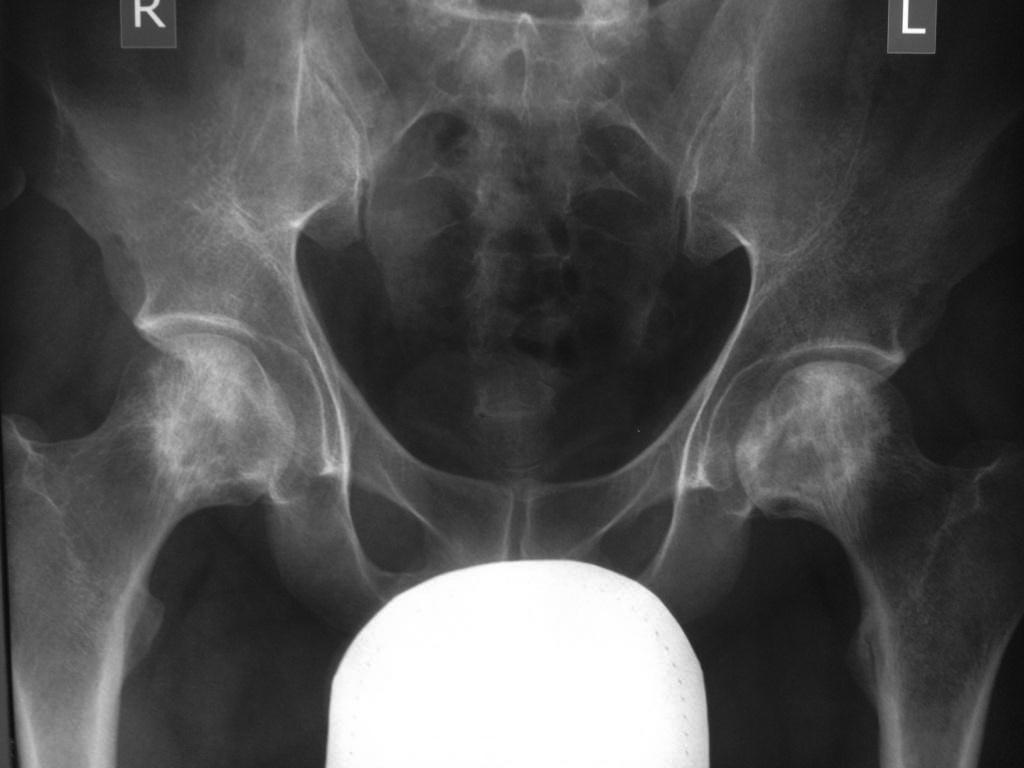

AVN. Синонимы: ишемический костный некроз, костный инфаркт, костный некроз, асептический некроз.

Возможно сомнения в диагностике связаны с нетипичной рентгенологической картиной. На снимке большая киста, которая расположена в центре головки, а при АВН начинается в верхней нагрузочной зоне. Отсутствует коллапс, сохранилась сферичность головки; не очень выраженный, но характерный признак "Crescent Sign".

Диффернциальную диагностику надо делать с доброкачественной кистой или метастазами. Но двухсторенная киста встречается очень редко, и киста в шейке распологается более дистально, чем при АВН. Гетерогенная картина головки немного напоминает метастаз, но без первичной опухоли и затяжной характер течения заболевания снимает подозрение на злокачественный процесс.